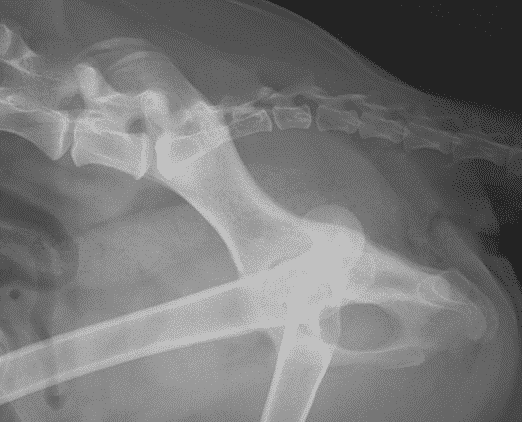

Even though there is limited association between radiographic and clinical signs of dysplasia, when both are severe, dogs are likely to benefit from early total hip replacement (Figures 1 and 2). In young dogs, the typical example is an eight- to nine-month-old medium to large-breed dog with luxoid hips which cannot walk for more than 10 to 20 minutes (Figure 2). These patients often only partially respond to conservative management and waiting for too long before a total hip replacement surgery may compromise its outcome. These dogs may experience remodelling of their proximal femoral metaphysis and diaphysis which may preclude the use of conventional implants or the chronically luxated hip may be extremely challenging to reduce in the future.